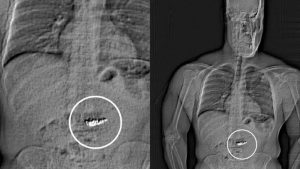

وبعد مطاردة قصيرة، قبضت الشرطة الأمريكية على الرجل بتهمة العصيان لأوامرها. وعند إخضاعه للفحص الطبي في مركز الاحتجاز، اكتشف المسؤولون وجود الأقراط داخل معدته.